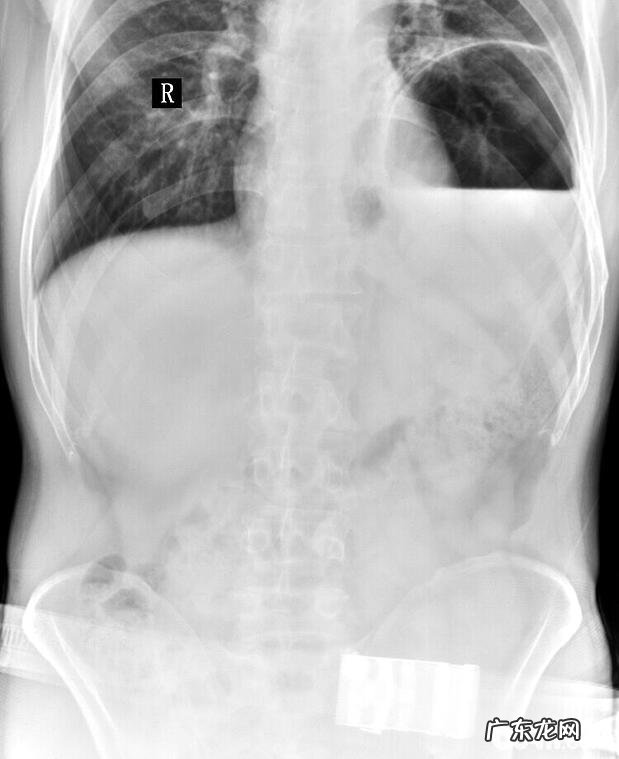

图2 X射线检查图

从图2显示信息,右边胸骨中后侧相对密度上升,心膈角消退,膈的轮廊消退,腹部内打气肠道的部位移位 。图2能够见到基本上全部胸骨的相对密度均上升,膈的轮廊消退,心血管的轮廊、形状不清楚 。

依据之上查验的結果能够诊断该犬因为车祸事故引起膈疝 。